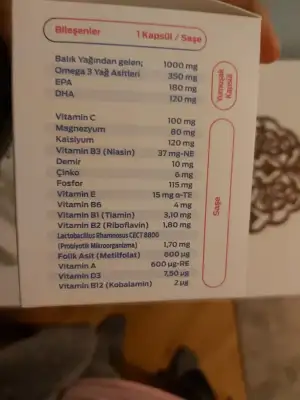

Ne için miş bunlar sorsaydın... bana Demir ve d vitamini verdi onları kullanmaya başladım 4 gündürBunlar verdikleri siz ne içiyorsunuz benim kafam karıştı

Toz olan multivitamin hepsi içinde varmış takipli gittiğim kendi doktorum.verdi..diğer doktorun verdiği kan hapı yine vitamin ve magnezyum verdi ayriyetten neden kan hapı vermemiş dedi bunları iç onun yerine dedi bende tozu içiyorum zorla..gittiğimde kontrole bitmiş olcak zaten içemiyorum diycem midemi bulandırıyor bitek vitamini içmiyorum hapı aynı diyeNe için miş bunlar sorsaydın... bana Demir ve d vitamini verdi onları kullanmaya başladım 4 gündür

Toz olan multivitamin hepsi içinde varmış takipli gittiğim kendi doktorum.verdi..diğer doktorun verdiği kan hapı yine vitamin ve magnezyum verdi ayriyetten neden kan hapı vermemiş dedi bunları iç onun yerine dedi bende tozu içiyorum zorla..gittiğimde kontrole bitmiş olcak zaten içemiyorum diycem midemi bulandırıyor bitek vitamini içmiyorum hapı aynı diye

Decaviit çok iyi canıım benim ablamda kullanmıştı araştırabilirsinKızlar ya kendi doktorum bana toz vermişti iğrenç ya içemiyorum zaten midem bulanıyor multivitamini 200 lira verdik bide..ikili test yaptığım dr tanıdıkdi başka dr yaptı yani bunu içme dedi ayriyetten demir hapı magnezyum ve decavit diye birşey yazdı napim ben bilemedim herkes birşey diyor toz olanda demir çok düşük ayriyetten demir hapı icmen gerekiyor diyor herkes

Bizde vitaminlere haftaya doktora gideceğimizde kontrolde başlayacağız öyle demişti doktoruum verdiği ilaçları atarıım canıımsizeBunlar verdikleri siz ne içiyorsunuz benim kafam karıştı

Tamam canım toz almayın sakın ya çok kötü ben heyecandan sormadım da ne yazdın diye bulantı var suyla ilaç iğrenç oluyorBizde vitaminlere haftaya doktora gideceğimizde kontrolde başlayacağız öyle demişti doktoruum verdiği ilaçları atarıım canıımsize